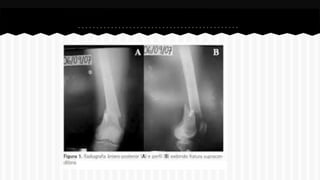

RESPONDA O NOME DO OSSO EM QUE

SE ENCONTRA A (S) FRATURA (A).